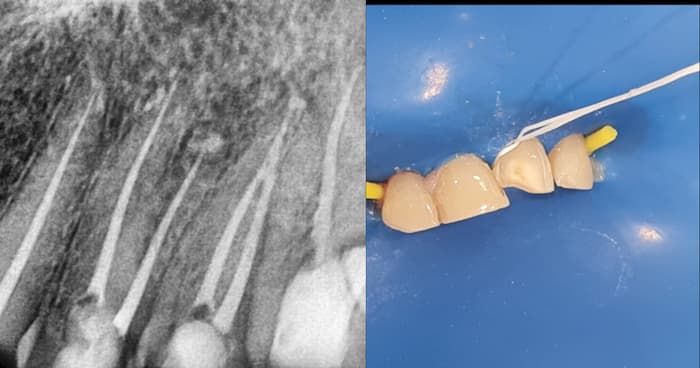

If a periapical radiolucency is present in a tooth (dark spot on an X-ray), this indicates chronic and more significant infection that may take longer time to heal. So early detection in a routine checkup prevents the spread to the jaw bone.